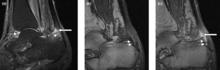

Magnetic resonance image of the index finger in psoriatic arthritis (mutilans form). Shown is a T2 weighted fat suppressed sagittal image. Focal increased signal (probable erosion) is seen at the base of the middle phalanx (long thin arrow). There is synovitis at the proximal interphalangeal joint (long thick arrow) plus increased signal in the overlying soft tissues indicating edema (short thick arrow). There is also diffuse bone edema (short thin arrows) involving the head of the proximal phalanx and extending distally down the shaft.